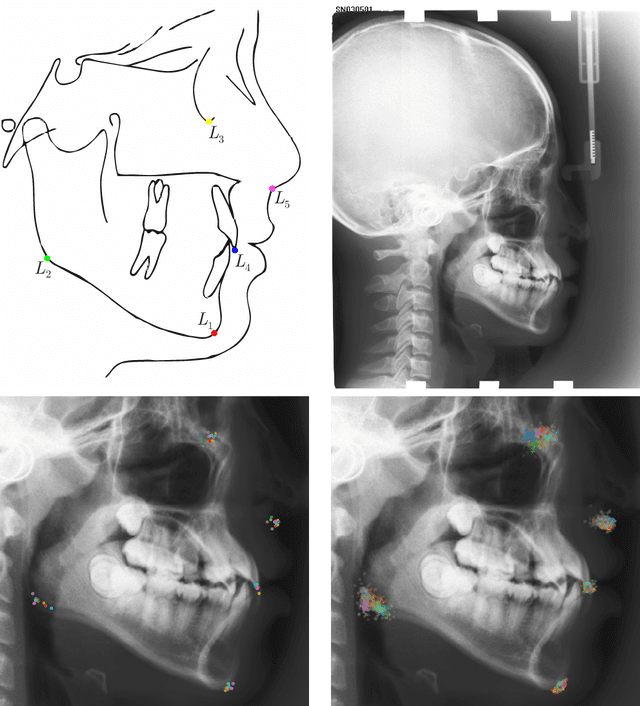

Abstract:In landmark localization, due to ambiguities in defining their exact position, landmark annotations may suffer from large observer variabilities, which result in uncertain annotations. To model the annotation ambiguities of the training dataset, we propose to learn anisotropic Gaussian parameters modeling the shape of the target heatmap during optimization. Furthermore, our method models the prediction uncertainty of individual samples by fitting anisotropic Gaussian functions to the predicted heatmaps during inference. Besides state-of-the-art results, our experiments on datasets of hand radiographs and lateral cephalograms also show that Gaussian functions are correlated with both localization accuracy and observer variability. As a final experiment, we show the importance of integrating the uncertainty into decision making by measuring the influence of the predicted location uncertainty on the classification of anatomical abnormalities in lateral cephalograms.